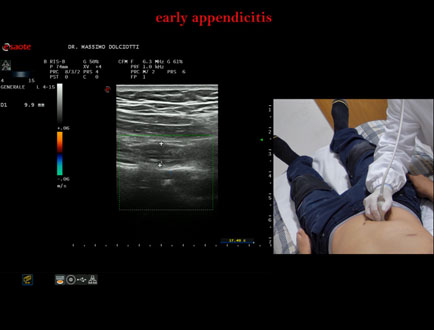

Età Paziente: M 26 anni

Motivazione dell'esame: da 2 settimane dolori addominali.

Commento all'esame: le immagini ed il video documentano il verme appendicolare, dello spessore trasversale di 9,1 mm e diametro longitudinale di 8,8 mm, con scarsi segnali di vascolarizzazione, da ricondurre ad appendicite in fase iniziale.

Conclusioni: appendicite in fase iniziale (early appendicitis).

Presentazione: Dr. Massimo Dolciotti - Ancona

Elaborazione digitale: Andrea Dini - Ancona